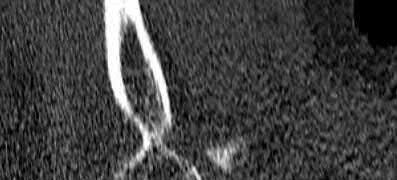

A 26-year-old male sustains an elbow injury after a fall from a skateboard resulting in valgus and supination forces across the left elbow. A CT scan of the left elbow is shown in Figures A through D. This fracture pattern is most commonly associated with what other traumatic elbow pathology?

The clinical presentation is consistent with a coronoid tip fracture. This fracture pattern is associated with a radial head fracture and posterolateral ulnohumeral dislocation - together making up the terrible triad injury.

A terrible triad injury is the result of a valgus and supination injury and involves posterolateral elbow dislocation or lateral collateral ligament injury, radial head fracture, and fracture of the coronoid process. The elbow may dislocate postero-laterally with the anterior bundle of the MCL intact, but if the MCL is injured it is typically the last structure to fail. The coronoid fracture is typically a small fragment isolated to the tip. This is a result of a posteriorly directed force driving the coronoid into the trochlea prior to posterior elbow dislocation. CT scan is a useful modality when small or comminuted fragments are difficult to visualize on plain radiographs.

Figures A through D show consecutive 2.00 mm sagittal CT reformats demonstrating a small coronoid fracture fragment which was addressed with suture fixation.